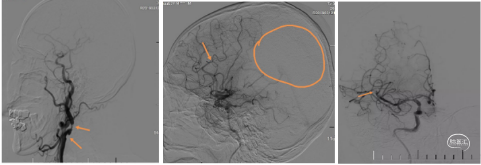

典型病例1 3*20小支架联合5F中间导管用于A2段SWIM取栓

患者男,59岁,右侧肢体活动不灵1小时25分钟。神经系统:神志清楚,反应迟钝,言语基本流利,双侧额纹、鼻唇沟对称,伸舌左偏,四肢肌张力正常,右上肢肌力3级,右下肢肌力2级,右侧巴氏征(+)。NIHSS评分9分。 ASPECTS-CT评分:前循环9分。MRI显示左侧大脑前动脉区域埂塞可能,MRA大脑前动脉A2以远未显影。

初步诊断:1.急性脑梗死(左侧大脑前动脉);TOAST分型:大动脉粥样硬化型);2.高血压病3级,很高危;3. 2型糖尿病。

造影右侧大脑前动脉缺如(未发育),左侧大脑前A2段闭塞。

发病位置与病因:左侧大脑前A2段,病因考虑动脉粥样硬化,不排除ICAS可能。

治疗方案:

大脑前动脉血管较细、路径迂曲,一般抽吸导管到位比较困难,又恐4mm及以上直径的取栓支架用于大脑前动脉对血管损伤较大,遂使用3*20mm小支架联合5F 125中间导管,SWIM取栓。

手术所用耗材:取栓支架 3*20mm、远端通路导管 5F 125cm 、0.014inch 300cm微导丝、2.4F微导管、6F长鞘、0.035in泥鳅导丝、5F造影导管。

手术过程:

1、微导丝越过闭塞处到达A3段。下图1

2、5F 125中间导管辅助高到位下图2。

3、手推造影明确血栓位置下图3。

4、微导管到达A4段下图4。

5、3*20取栓支架到位回撤微导管,多点显影标记,清晰可见支架打开良好下图5。

造影显示血管再通。